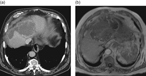

Primary choriocarcinoma of the liver: a rare, but important differential diagnosis of liver lesions

Alexander Kohler and others

Journal of Surgical Case Reports, Volume 2018, Issue 4, April 2018, rjy068, https://doi.org/10.1093/jscr/rjy068